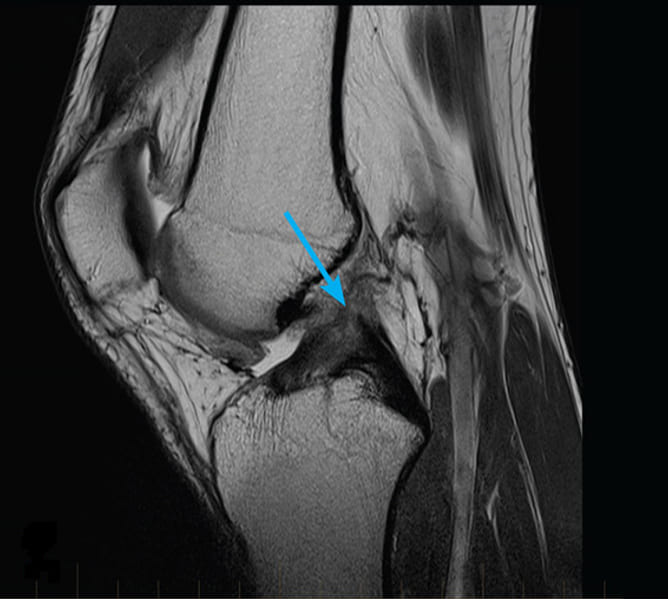

Podívejte se na tyto obrázky, můžete vidět, že na obrázku vpravo není žádný kloubní prostor, kosti se o sebe třou a způsobují silnou bolest. A tento proces je velmi těžké zastavit! Za pár let se ten člověk stane invalidním a už se nebude schopen sám živit.

Markéta Svobodová: Především jsou to vážná zranění a napětí. Nadváha také hodně zatěžuje vaše klouby. Sedavý způsob života, stres, nadbytek soli a cukru ve stravě, to vše změkčuje chrupavčitou tkáň, opotřebovává ji a ředí. Při každém novém pohybu se chrupavka ničí a deformuje a kosti se o sebe začnou třít, což způsobuje nesnesitelnou bolest.